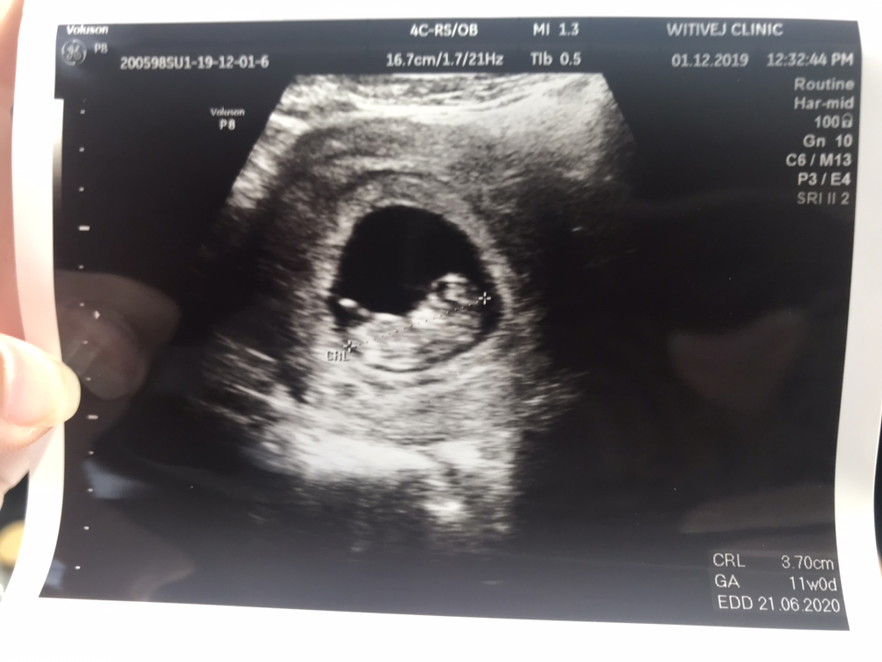

12วีค4วันค่ะ